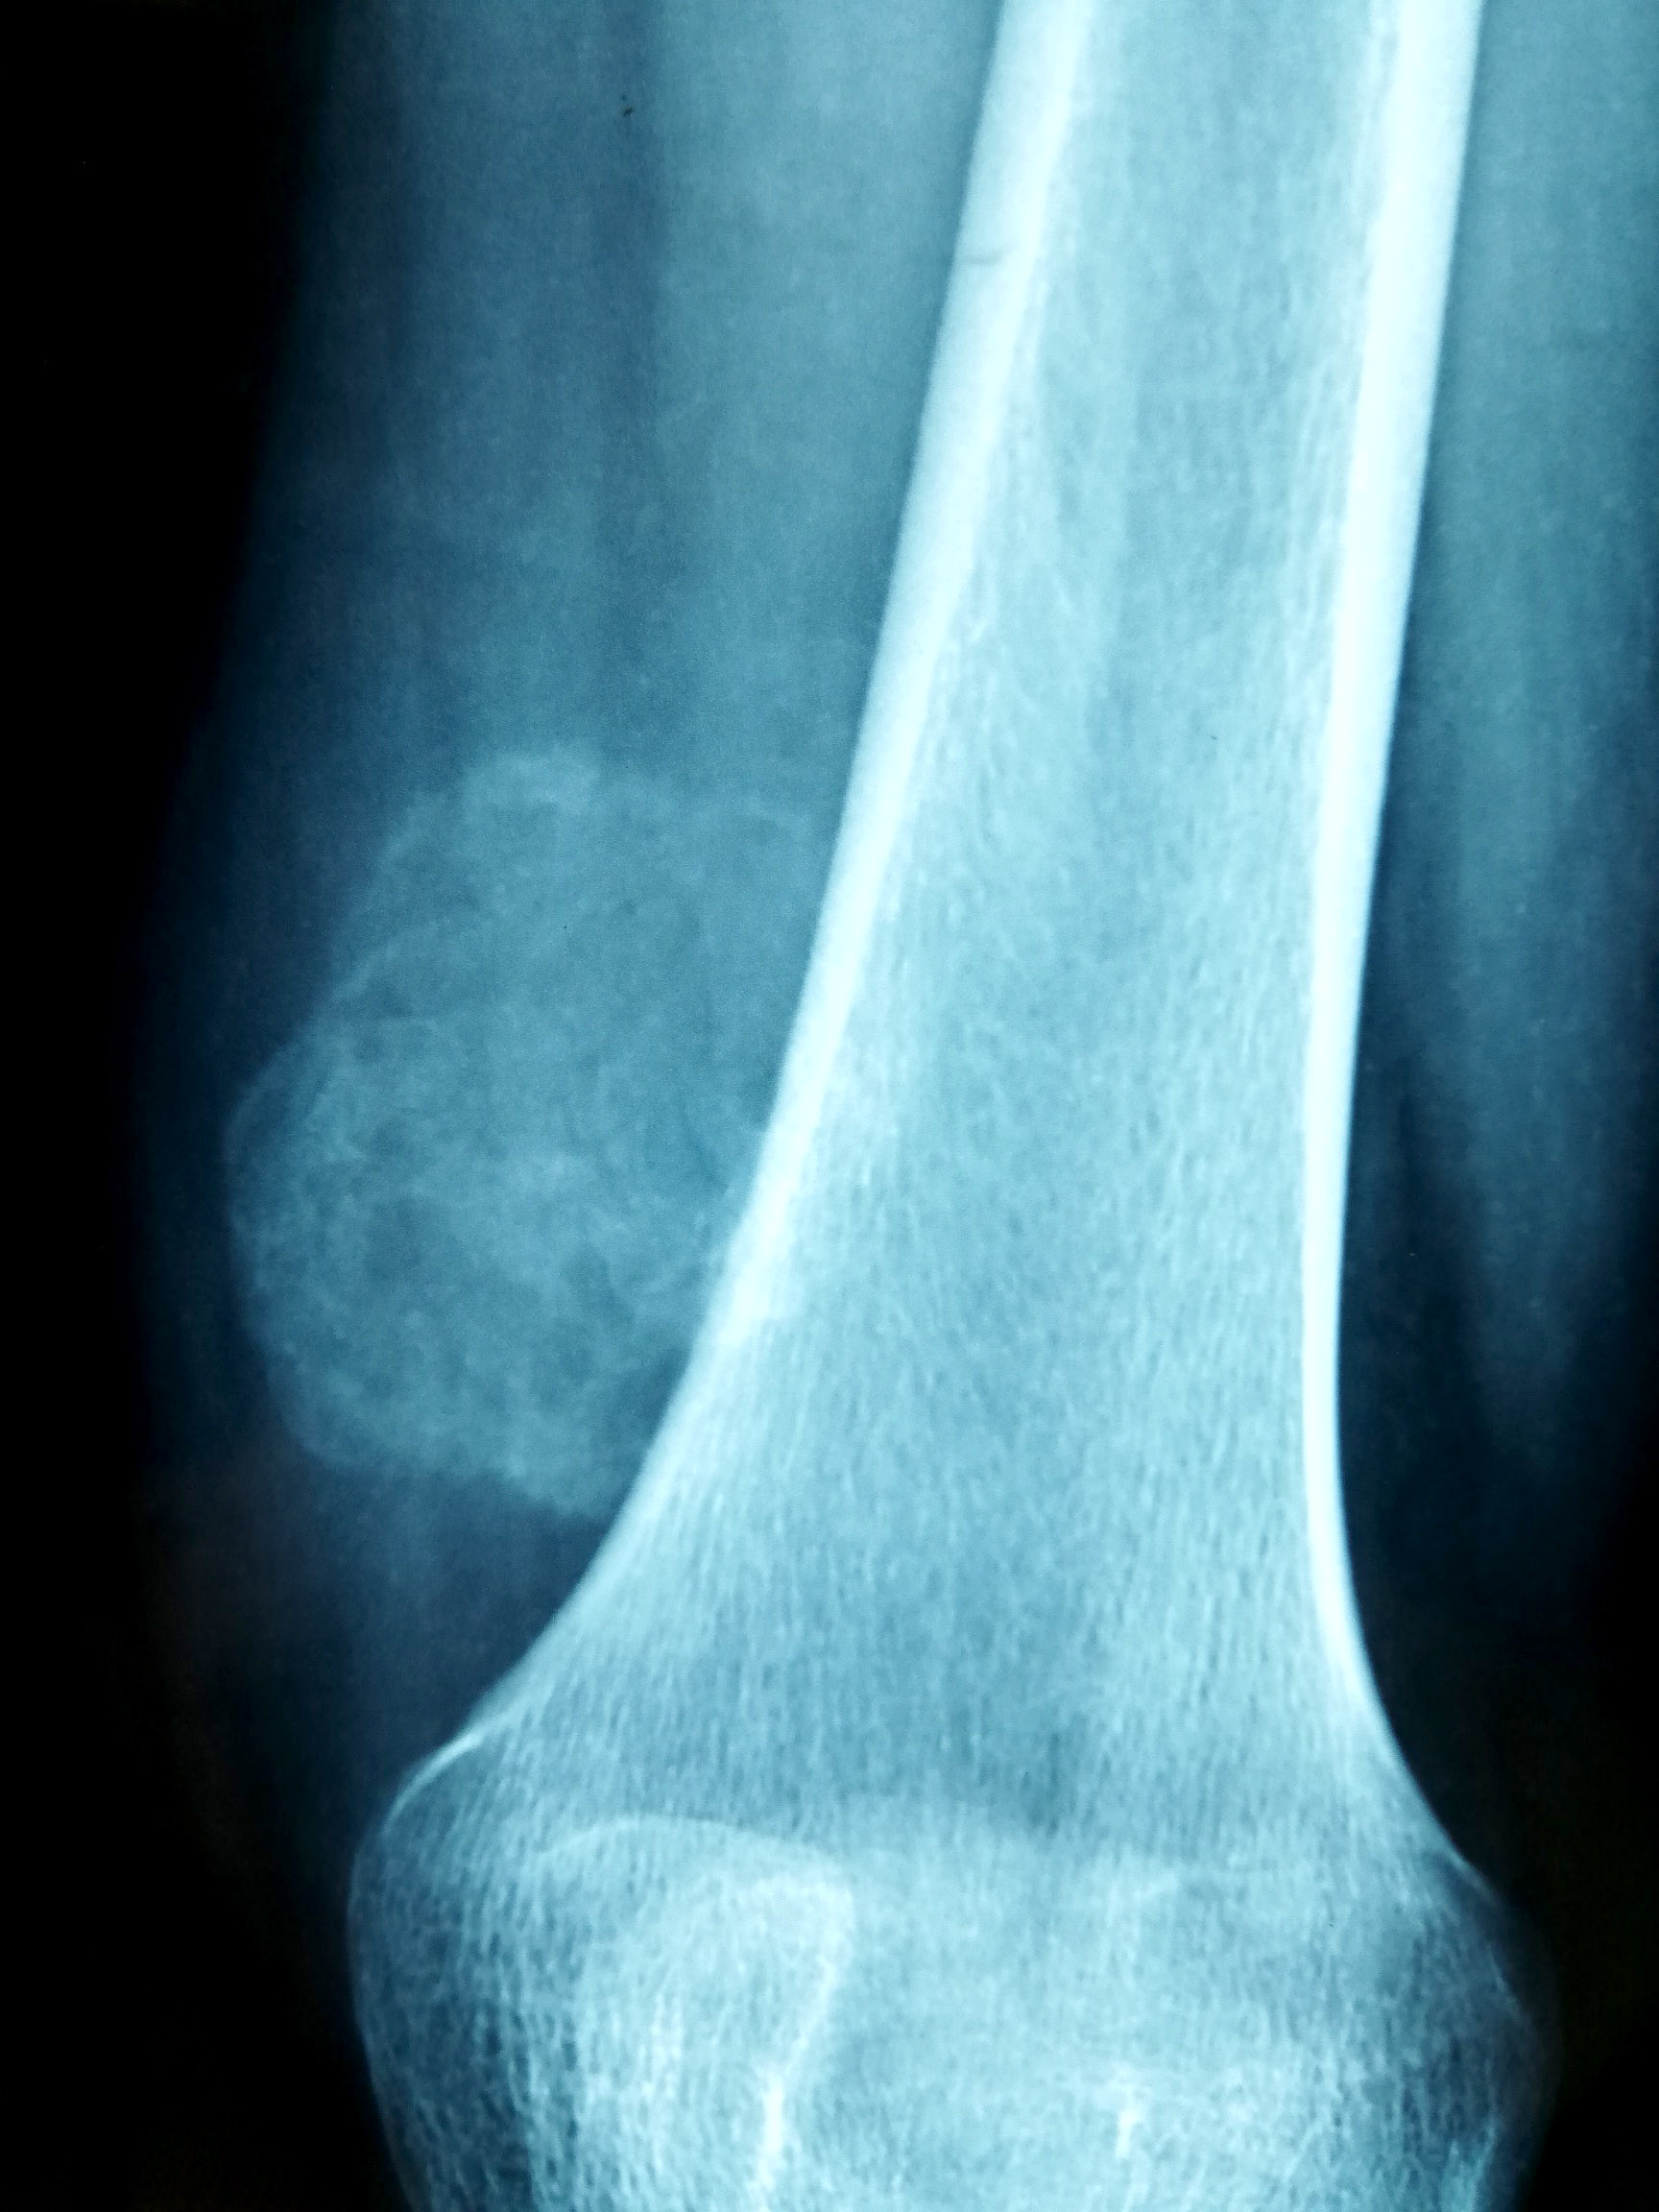

Radiology description

- Early stage:

- Xray: normal to faint calcification (flocculent radiopacities: dotted veil pattern)

- CT scan: soft tissue edema

- MRI: isodense on T1 and hyperintense on T2

- Intermediate stage:

- Xray: peripheral calcified rim with central lucency

- CT scan: peripheral mineralization with central low attenuation (calcification proceeds from periphery to center)

- MRI: isodense / hypodense to adjacent skeletal muscle on all images

- Mature, late stage:

- Xray: diffuse soft tissue calcification

- CT scan: diffuse ossification pattern (even in late lesions, the central core may remain uncalcified)

- MRI: well defined soft tissue mass and isodense to fat on all images

- References: Curr Sports Med Rep 2018;17:290, J Clin Orthop Trauma 2021;17:123

Radiology images